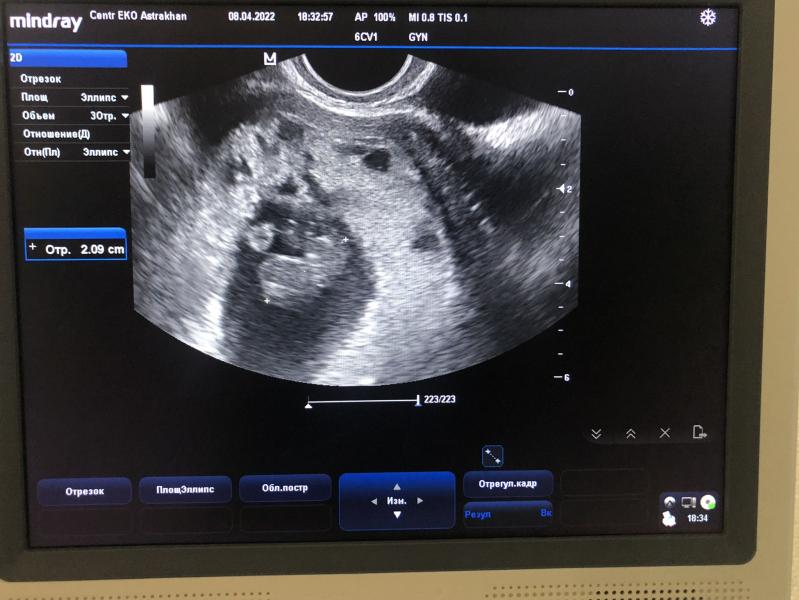

Репродуктолог назначила узи аж на 28дпп, конечно же я не могла столько ждать, терпела как могла, но на 20дпп начал тянуть живот и я вроде как нашла себе оправдание, что надо проверить все ли там хорошо, на 21дпп побежала к Лакомской на узи, та посмотрела, беременность маточная все хорошо плодное яйцо, размеры все ок, эмбриона и сердцебиения тогда еще не было.

На 7ой день пребывания в стационаре, меня отправляют впервые на узи, сколько бы я до этого не просила, говорили не положено. Стояла у дверей кабинета узи и меня трясло как лист на ветру, хоть и кровь остановилась уже на 2ой день пребывания там, меня пугало, что токсикоз пропал вместе с кровотечением, я готовилась к самому страшному.

Зашла в кабинет, начали делать узи, доктор говорит отслойка сократилась, эмбрион есть, включает сердцебиение, у меня все внутри перевернулось и я зарыдала 🫣 я мыслено уже была готова к негативному результату, а моя девочка, мой боец, знает как бороться за жизнь и это не последний случай когда она это докажет🙌🏻🫶🏻